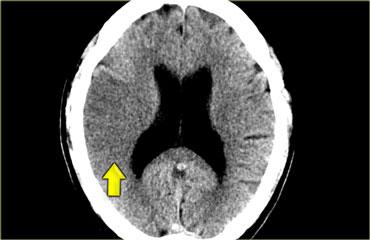

Hình bên trái là bệnh nhân có mô não giảm tỷ trọng ở bán cầu phải.

Chẩn đoán là nhồi máu não, dựa trên vị trí tổn thương (vùng tưới máu của động mạch não giữa – MCA) và sự liên quan của cả chất xám lẫn chất trắng, đây cũng là đặc điểm rất điển hình của nhồi máu não.

Giảm tỷ trọng trên CT có độ đặc hiệu cao cho tổn thương não thiếu máu không hồi phục nếu được phát hiện trong 6 giờ đầu (1).

Những bệnh nhân có triệu chứng đột quỵ và biểu hiện giảm tỷ trọng trên CT trong sáu giờ đầu đã được chứng minh là có thể tích nhồi máu lớn hơn, triệu chứng nặng hơn, diễn tiến lâm sàng kém thuận lợi hơn và thậm chí có nguy cơ xuất huyết cao hơn.

Do đó, bất cứ khi nào bạn thấy giảm tỷ trọng ở bệnh nhân đột quỵ, đây là dấu hiệu tiên lượng xấu.

Không có giảm tỷ trọng trên CT là dấu hiệu tốt.